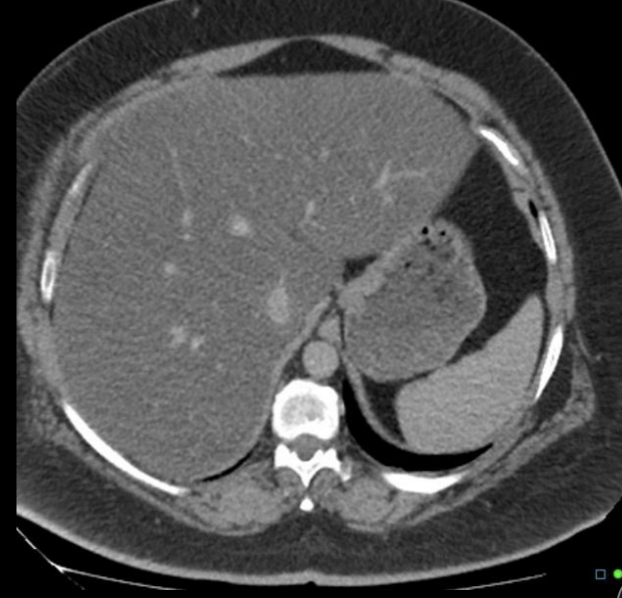

4

Q

A

Normal